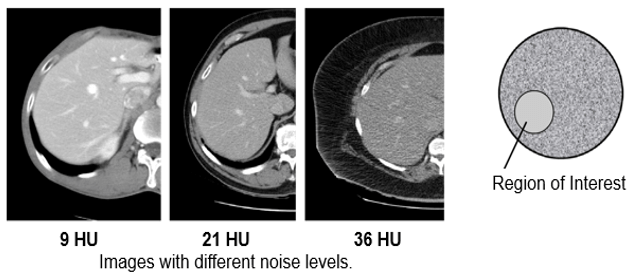

Noise is a set of incoherent signals that degrade the images. Noise in CT is an unwanted change in pixel values in an otherwise homogenous image.

Noise in CT is measured via the signal to noise ratio (SNR) by comparing the level of the desired signal (photons) to the level of background noise (pixels deviating from normal). CT images have been reconstructed from raw data using filtered back projection (FBP) since the inception of the modality.

Standard Deviation SD

The standard deviation is the deviation of CT numbers (Hounsfield Units) in the region of interest. The acceptable limits for the CT Number Standard Deviation Test should be the Standard Deviation of water not exceeding a level specified by the manufacturer.